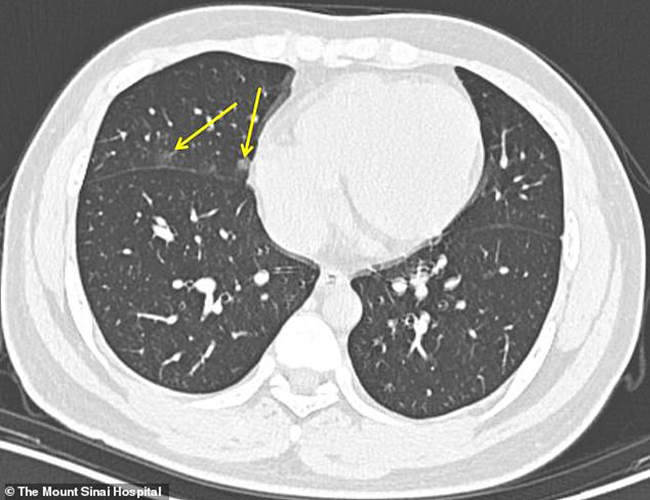

Ảnh chụp CT của bệnh nhân 15 tuổi, người từng đến Vũ Hán du lịch. Hình ảnh chụp CT được thực hiện sau 3 ngày kể từ khi có các triệu chứng nhiễm virus. Các nhà nghiên cứu đã tìm thấy những phát hiện mơ hồ trong phổi là dấu hiệu của coronavirus, không phải là dấu hiệu điển hình của các bệnh phổi khác. Mũi tên chỉ vào dấu hiệu của virus. (Ảnh: Dailymail)